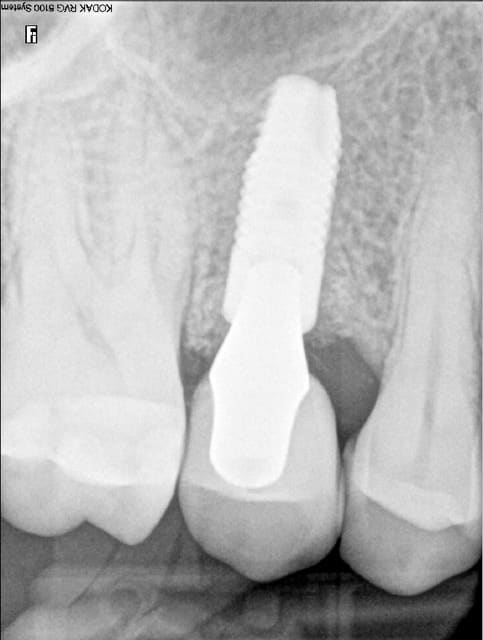

Et finalement: la dent, l'implant est pas parfaitement posé mais le résultat global est satisfaisant.